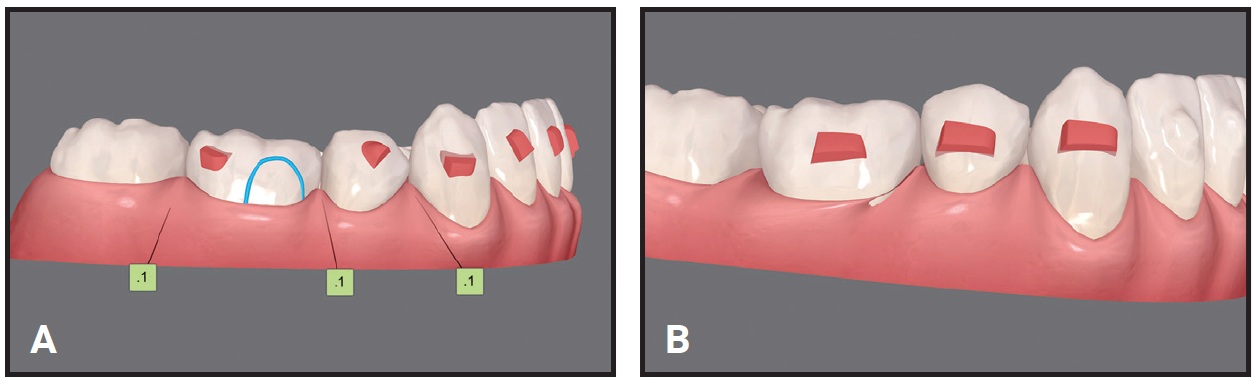

As my office developed digital design systems, we found that mistakes in mesiodistal orientation during LightForce* planning could result in narrow point contacts that produced food traps (Fig. 3). Similarly, unresolved tip issues in planning Invisalign** treatment could lead to unwanted food traps (Fig. 4).

Although these corrections may appear somewhat minor, food traps can be annoying for patients, even changing their perspective on treatment results. The clinician’s immediate response might be to add closing chain with fixed appliances or virtual interproximal reduction (overcorrection) with aligners. We’ve found that paying close attention during the initial planning stages can significantly reduce these problems.